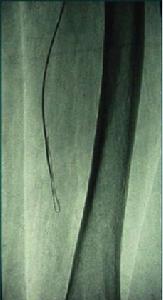

導絲、導管進入內膜下後,推進導絲向動脈遠側前行,導絲頂端需突破管壁組織的障礙,因此導絲常常向管壁組織最薄弱的方向前行,造成導絲在內膜下前行並非成直線,而是彎曲成襻狀(圖一)。